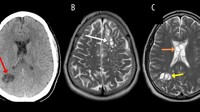

Larva cacing pita parasit ditemukan di otak seorang pria (52) Amerika Serikat yang mengeluh mengalami migrainnya selama berminggu-minggu. Infeksi cacing pita ini diyakini disebabkan oleh konsumsi daging yang kurang matang. (Foto: American Journal of Case Reports).